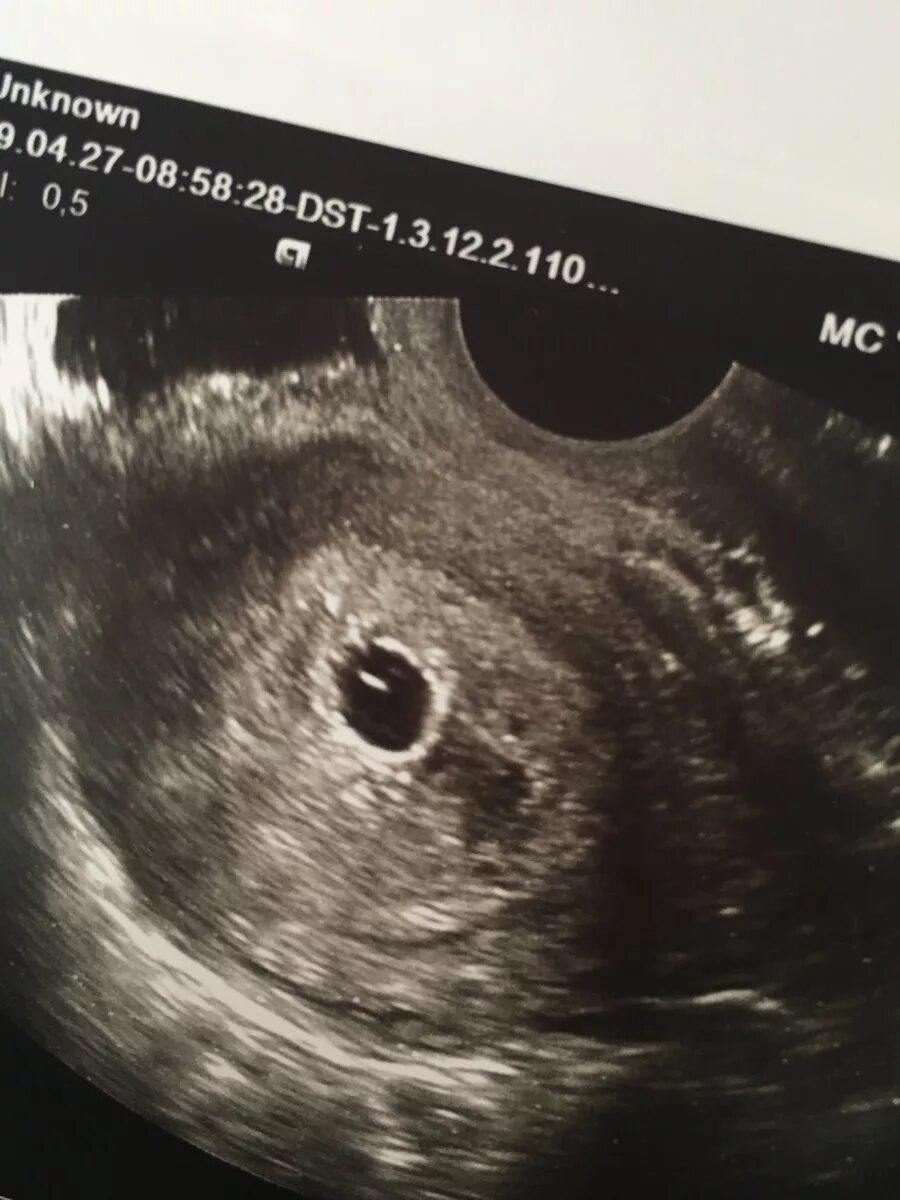

Плодное яйцо желточный мешочек